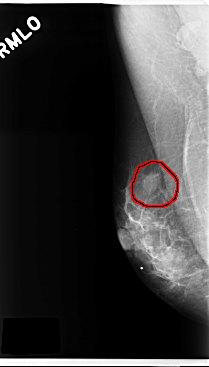

C_0270_1.RIGHT_MLO

RIGHT_MLO LINES 4760 PIXELS_PER_LINE 2712 BITS_PER_PIXEL 12 RESOLUTION 50 OVERLAY

FILE: C_0270_1.RIGHT_MLO.OVERLAY

TOTAL_ABNORMALITIES 1

ABNORMALITY 1

LESION_TYPE MASS SHAPE OVAL MARGINS CIRCUMSCRIBED

ASSESSMENT 3

SUBTLETY 5

PATHOLOGY BENIGN

TOTAL_OUTLINES 1

BOUNDARY